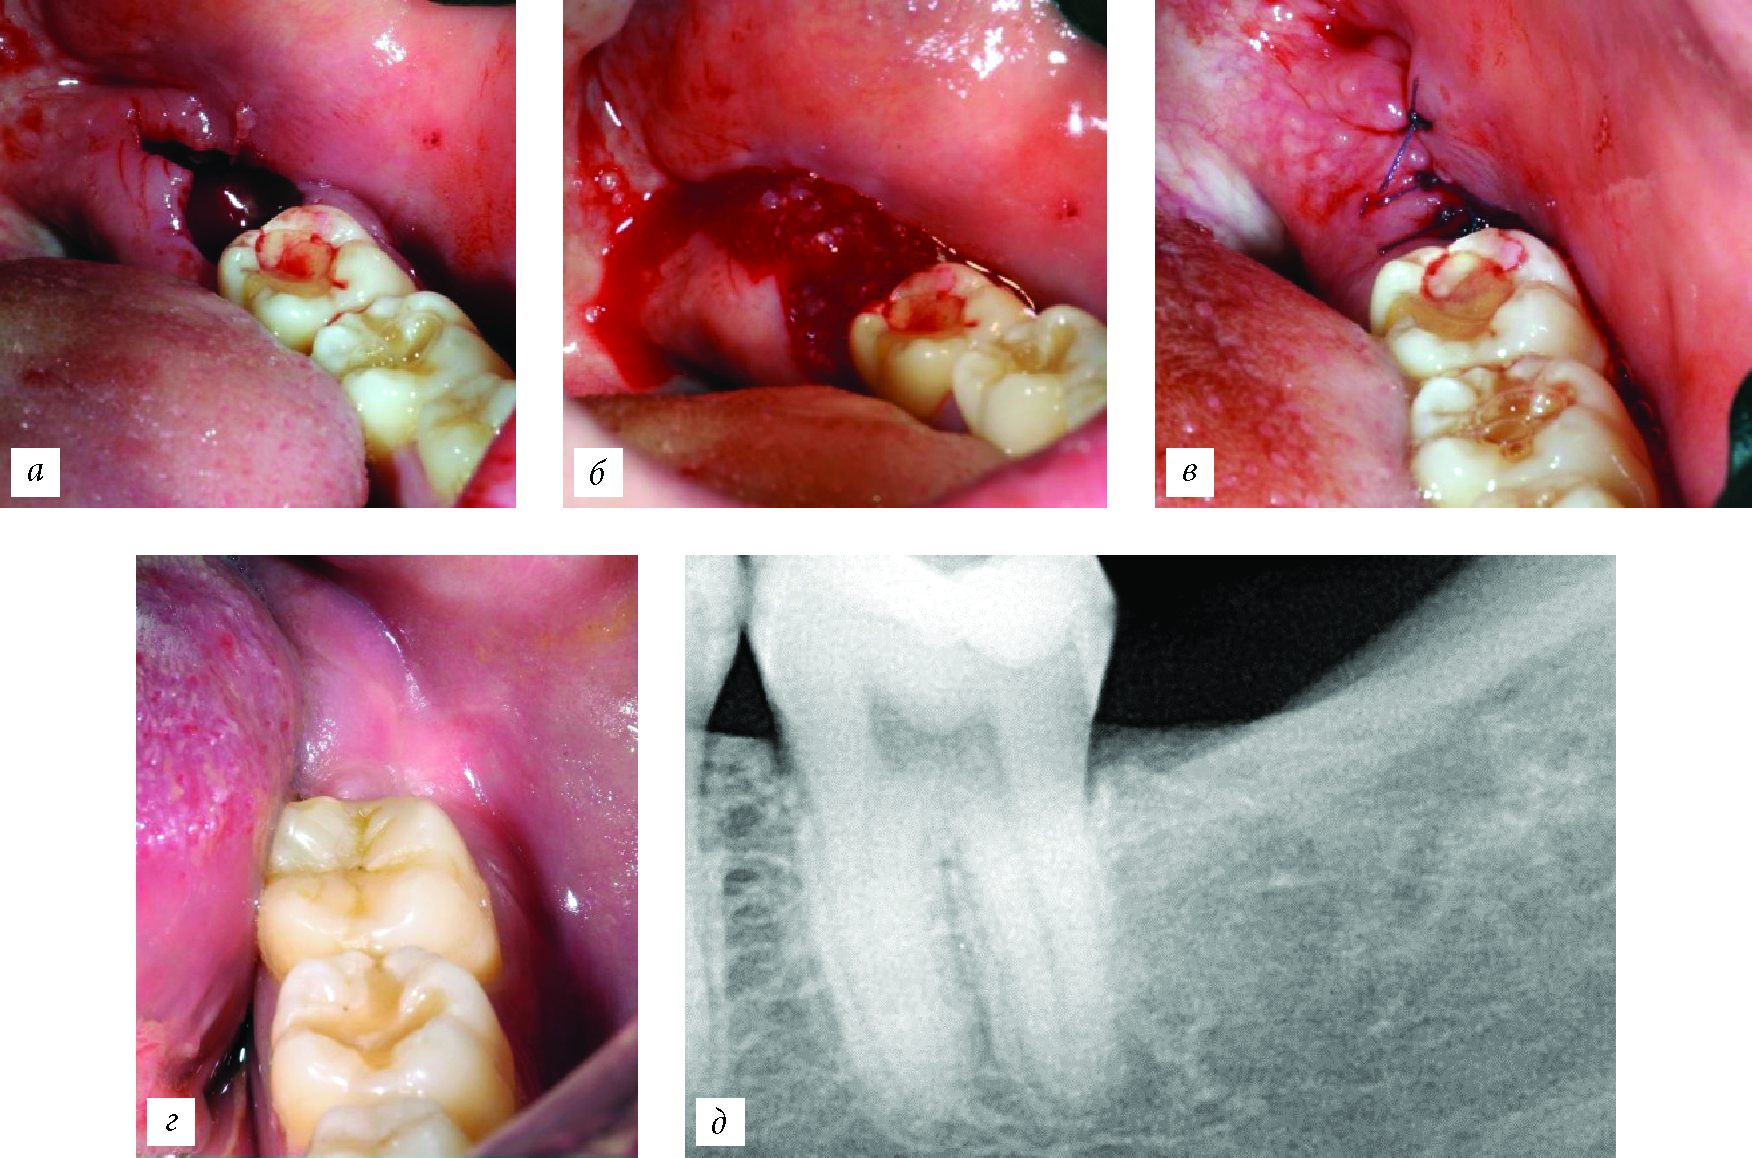

В 1-й группе исследования у двух пациентов, после удаления зубов и у одного пациента после удаления ретенированного зуба была выявлена частичная самопроизвольная элиминация используемого материала в связи с расхождением краев раны (рис. 6), что, очевидно, было связано с погрешностями в наложении швов, а не с реакцией организма на материал (в том числе с развитием гидротопического отека).

Рис. 6. Заживление послеоперационной раны. а — элиминация материала; б — эпителизация материала при заживлении без осложнений.

Необходимо отметить, что исследуемый коллагеновый материал достаточно сложно поместить в дефект, если в костной ране отсутствует более одной стенки, из-за его желеобразной консистенции. Применение в качестве смешивающего раствора крови пациента не влияет на физические свойства мате-риа-ла (рис. 7). Применение материала для профилактики постэкстракционной атрофии в сравнении с контрольной группой позволило уменьшить атрофию костной ткани в послеоперационном периоде и создать более благоприятные условия для отсроченной дентальной имплантации даже в случаях частичной элиминации материала.

Рис. 7. Применение материала коллагенового материала, смешанного с физиологическим раствором. а — костный дефект после удаления ретенированного зуба; б — заполнение костного дефекта материалом; в — глухой шов послеоперационной раны; г — полость рта через 3 мес после хирургического вмешательства; д — рентгенограмма через 3 мес после хирургического вмешательства.

Во второй группе исследования (заполнение костного дефекта порошком коллагенового материала в сочетании с PRF), осложнения были выявлены у одного пациента. Через 8 мес. после цистэктомии с резекцией верхушки корня возник рецидив гранулематозного периодонтита, который был обусловлен не применением материала, а, скорее всего, погрешностями в эндодонтическом лечении. Добавление I-PRF к ксеноколлагену позволяет получить более стабильную консистенцию материала, который при загустевании приобретает форму дефекта и упрощает работу с ним (рис. 8). Достоверных различий влияния материала на постэкстракционную атрофию в обеих группах исследования получено не было (p > 0,05), а в сравнении с контрольной группой применение материала позволило уменьшить атрофию костных и мягких тканей (p < 0,05).